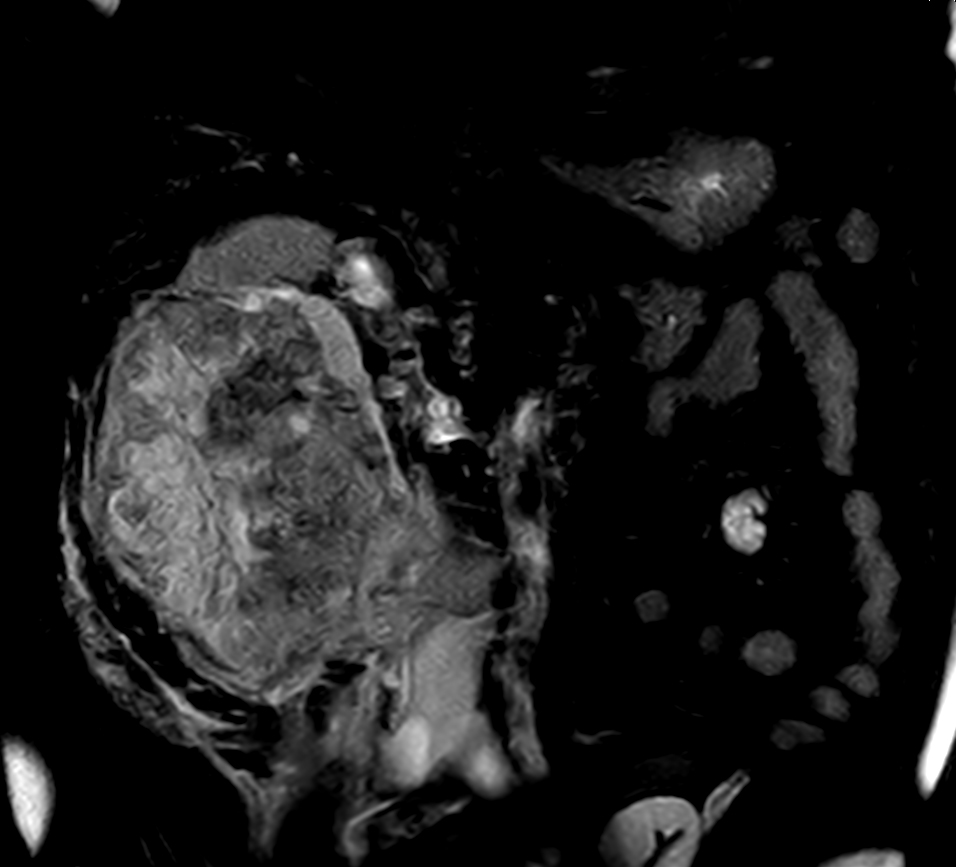

Patient with kidney tumor. ExamCard includes Compressed SENSE to shorten the breath hold time, VitalEye for touchless respiratory sensing, mDIXON XD FFE to acquire up to four image types in one single scan, DWIBS to achieve high contrast between background and lesions and bTRANCE for non-contrast time-resolved imaging.

bTFE - VitalEye Compressed SENSE